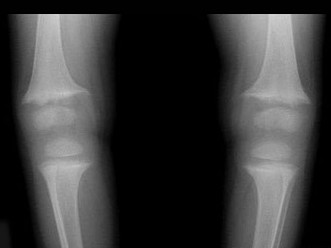

C.维生素D缺乏症

D.维生素C缺乏症